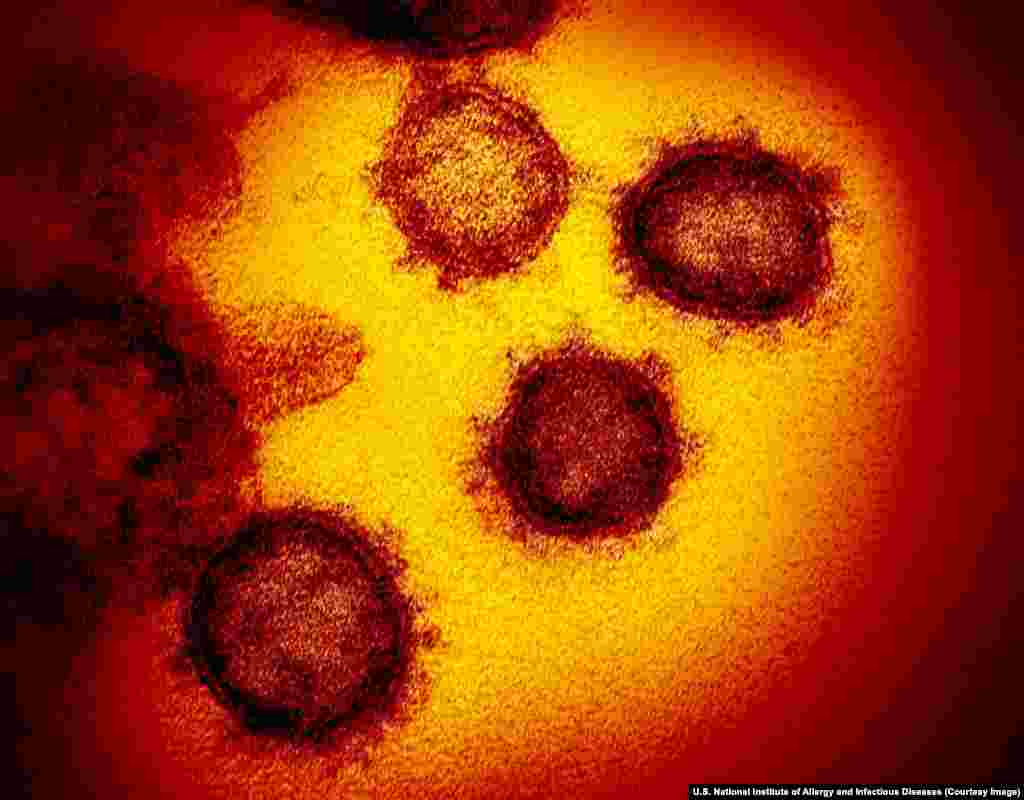

1

Disa copëza të virusit Covid-19 përmes mikroskopit elektronik. Për koronavirusin e ri është raportuar fillimisht në qytetin kinez, Vuhan në fund të vitit 2019. Deri më fund të muajit prill, ky virus ka lënë më shumë se 36,000 persona të vdekur.